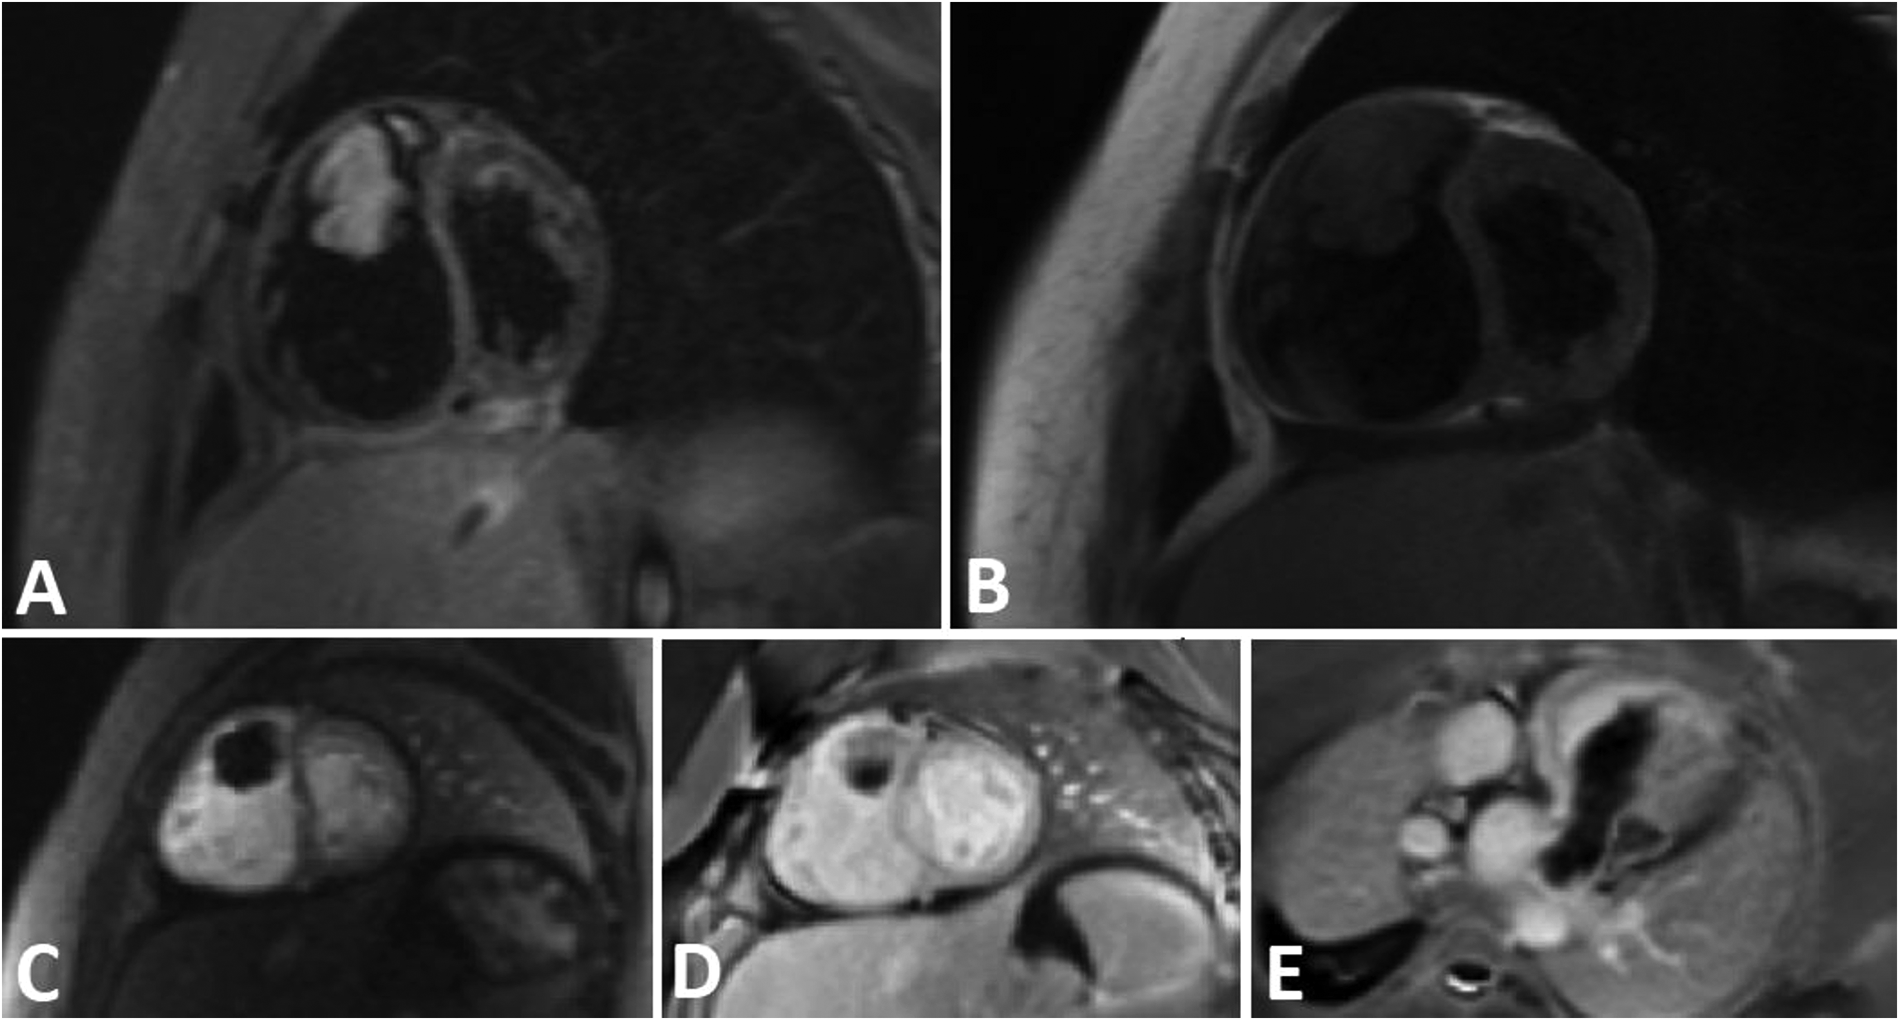

Cardiac magnetic resonance (CMR) imaging was conducted to investigate non-thrombotic causes (Figure 2), and subsequently, she was transferred to the operation room for surgical intervention.

Figure 2

A tubular shape tumor in RVOT and protrusion in to the main PA. (A) Short axis view STIR sequence demonstrates high signal tumor. B) Short axis view T1-W sequence reveals Iso signal tumor. (C) Short axis view perfusion sequence shows no early enhancement. (D,E) Short axis and oblique view Late Gadolinium Enhancement (LGE) sequence demonstrates faint enhancement at some part of the tumor.